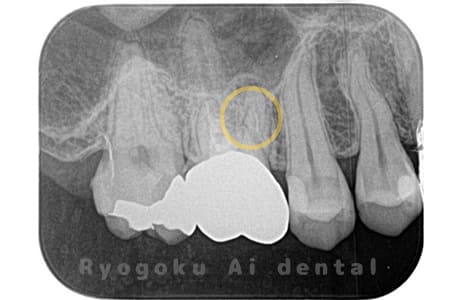

Case02

-

- 原因

- 慢性根尖性歯周炎

- 治療期間

- 3ヶ月

- 治療内容

- マイクロエンド

- 治療費用

- 121,000円

噛むと痛みが出る、とのことで来院した患者様です。他院での根管治療を終えてましたが、根尖病変を認めるため、マイクロエンドを行いました。